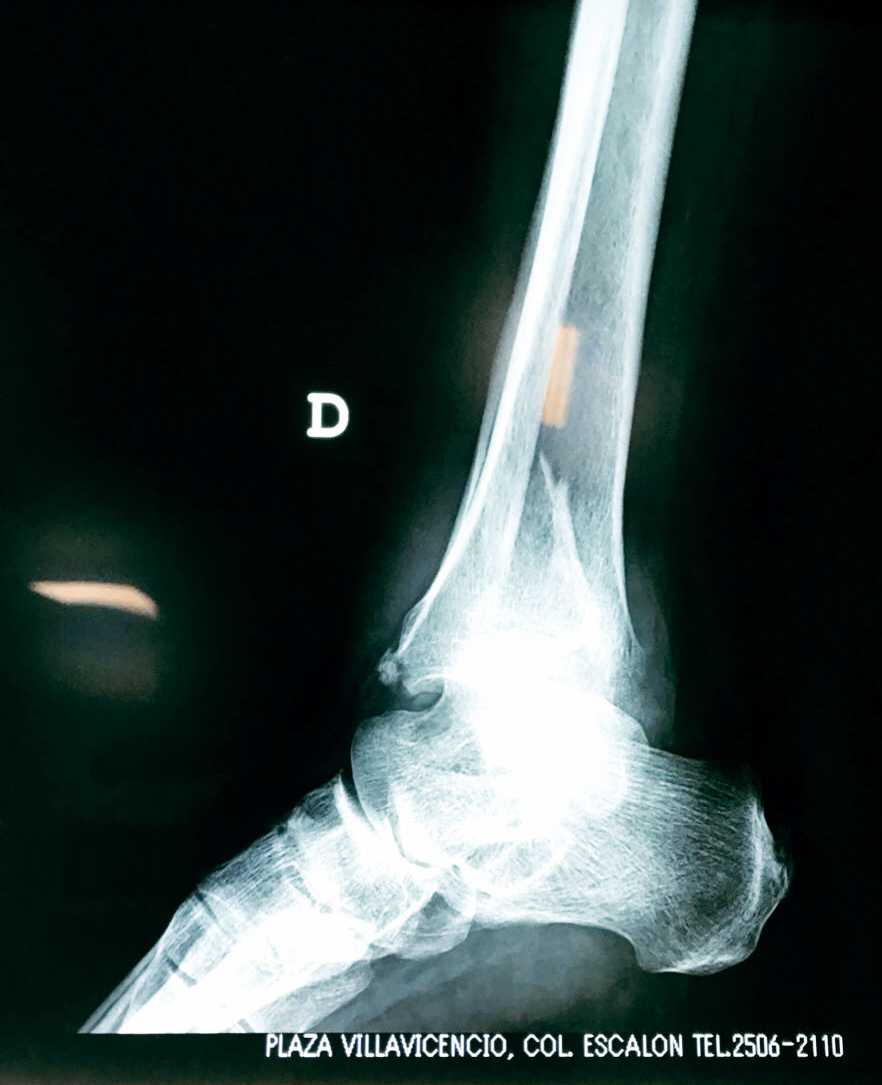

Una fractura de tobillo es la rotura de uno o más de los huesos del tobillo. Estas fracturas pueden ser:

Algunas fracturas de tobillo pueden requerir cirugía si:

- Los extremos de los huesos están desalineados entre sí (desplazados).

- La fractura se extiende hasta la articulación del tobillo (fractura intra-articular).

- Los tendones o ligamentos (tejidos que sujetan los músculos y los huesos entre sí) están rotos.

- El médico cree que sus huesos probablemente no sanen apropiadamente sin cirugía.

- El médico considera que la cirugía puede permitirle una recuperación más rápida y confiable.

- En los niños, la fractura involucra la parte del hueso del tobillo donde el hueso está creciendo.